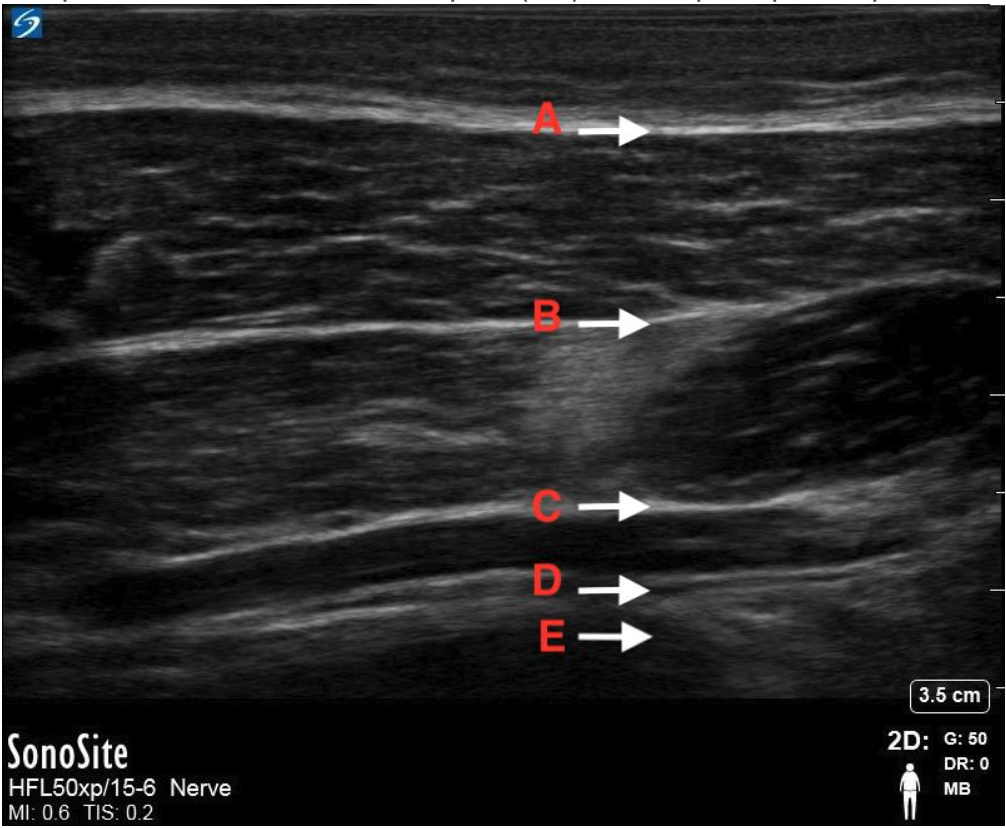

Between what layers is local anesthesia deposited for a TAP block in the following image?

C

Transverse Abdominis and Internal Oblique

“TI the TAP”